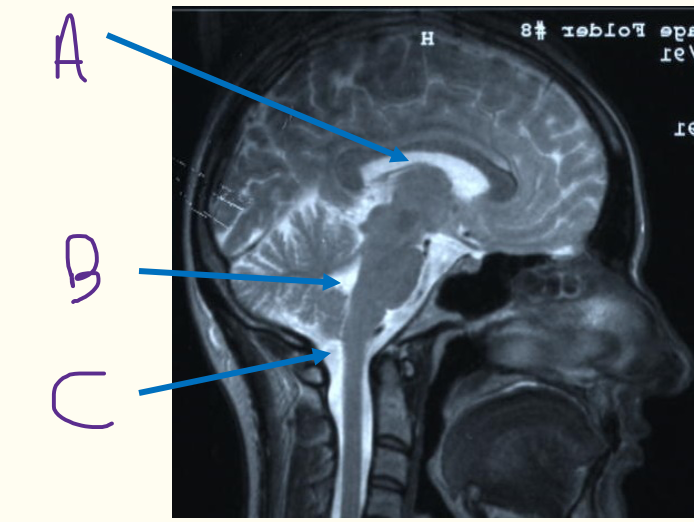

HYDROCEPHALUS

i) what type of hydrocephalus is being represented by the pictures?

ii) is the MRI T1 or T2 weighted?

iii) explain the treatment shown

i) non communicating hydrocephalus

ii) T2 weighted as fluid is white

iii) shunt from lateral ventricle to abdomen to decrease ICP